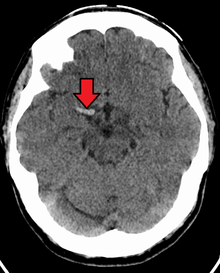

Cerebral venous sinus thrombosis (CVST) is a rare form of stroke which results from the blockage of the dural venous sinuses by a thrombus. Symptoms may include headache, abnormal vision, any of the symptoms of stroke such as weakness of the face and limbs on one side of the body and seizures. The diagnosis is usually made with a CT or MRI scan. The majority of persons affected make a full recovery. The mortality rate is 4.3%.[10]